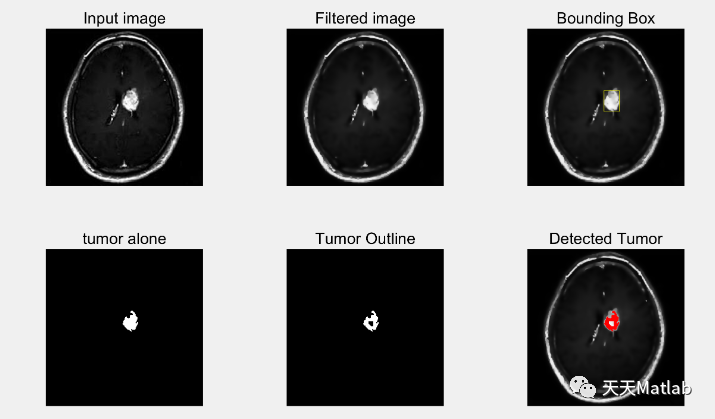

在医学领域,脑肿瘤的早期检测和准确诊断对患者的治疗和康复至关重要。近年来,随着计算机视觉和图像处理技术的快速发展,基于MRI图像的脑肿瘤检测成为研究的热点之一。本文将介绍一种基于各向异性滤波器和分割图像处理的方法,用于从MRI图像中检测脑肿瘤。

各向异性滤波器是一种经典的图像增强技术,可以有效地去除图像中的噪声,并增强图像的边缘信息。在脑肿瘤检测中,我们可以使用各向异性滤波器对MRI图像进行平滑处理,以减少噪声的干扰,并突出肿瘤的边缘特征。通过调整各向异性滤波器的参数,我们可以控制滤波器的平滑程度和边缘增强程度,从而优化脑肿瘤的检测效果。

在各向异性滤波器的基础上,我们还可以采用分割图像处理的方法来提取脑肿瘤的区域。分割是图像处理中的一项关键任务,旨在将图像分割成具有相似特征的区域。对于脑肿瘤检测,我们可以使用分割算法将MRI图像中的肿瘤区域与正常脑组织区域进行区分。常用的分割算法包括阈值分割、区域生长和基于图割的分割方法。通过将分割算法与各向异性滤波器相结合,我们可以更准确地提取脑肿瘤的区域,并进行进一步的分析和诊断。

总结起来,基于各向异性滤波器和分割图像处理的方法在MRI图像检测脑肿瘤方面具有很大的潜力。通过对MRI图像进行预处理和分割,我们可以提高脑肿瘤的检测准确性,并为医生提供更可靠的诊断依据。随着计算机视觉和图像处理技术的不断进步,我们相信脑肿瘤的早期检测和精确诊断将变得更加可行和可靠,为患者的健康和生活质量带来积极的影响。